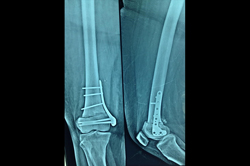

Distal Femur